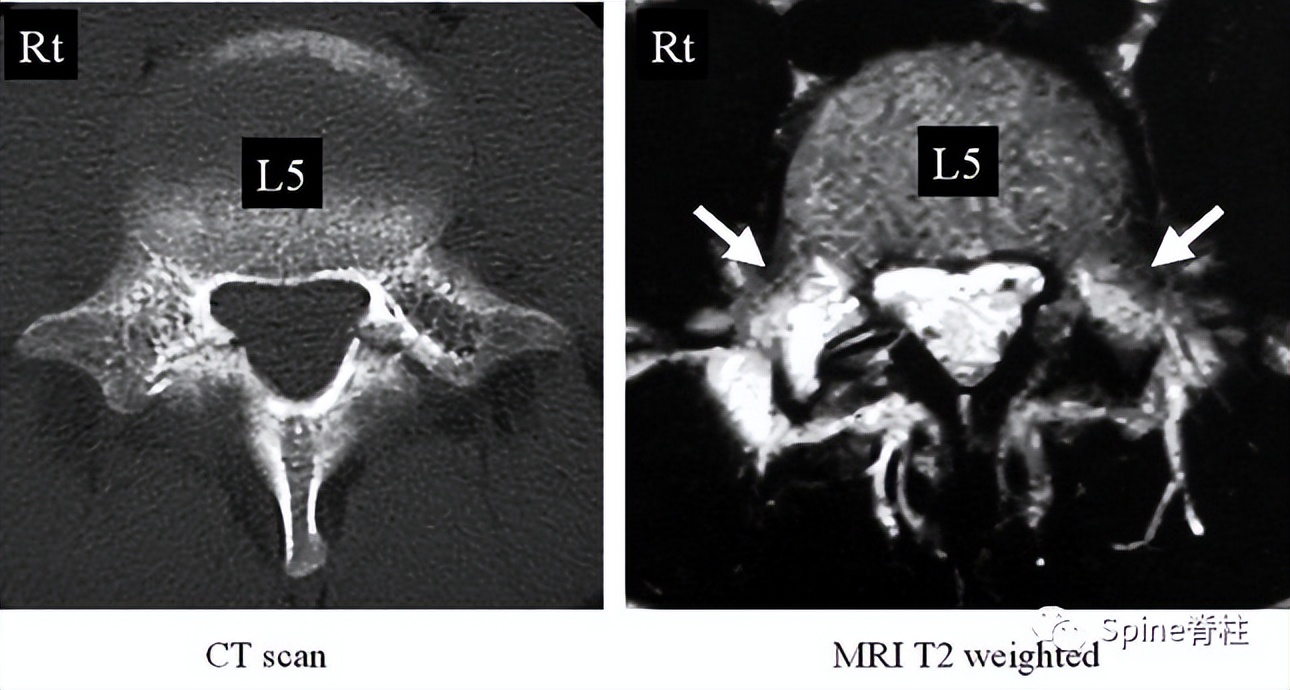

左侧为椎弓根水肿阳性,右侧为椎弓根水肿阴性,有研究发现峡部裂伴随着椎弓根水肿,支具固定愈合率更高

左侧早期峡部裂伴椎弓根水肿,支具固定6月后愈合

右图提示双侧椎弓根高信号改变(箭头)

右图:右侧椎弓根高信号改变明显,左侧椎弓根轻微高信号